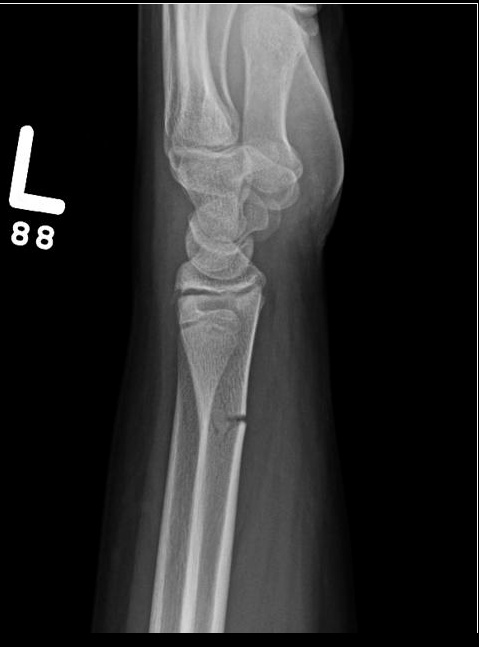

X-ray imaging will show a mid-diaphyseal break, usually with angulation and disruption of the cortical bone on the side of the fracture.

It may be necessary to break the bone on the concave side in order to achieve reduction of the fracture because the plastic deformation recoils it back to the deformed position. Immobilization with casting for 2-3 weeks allows this fracture to heal.